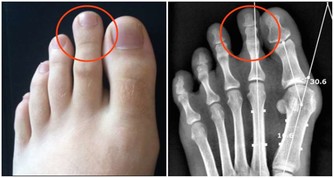

其實,不使用公筷是給細菌,尤其是幽門螺桿菌創造了傳播途徑。

幽門螺桿菌主要潛伏在胃粘膜組織中,人一旦感染這種細菌,就可能引起口臭、胃炎,甚至是胃癌。